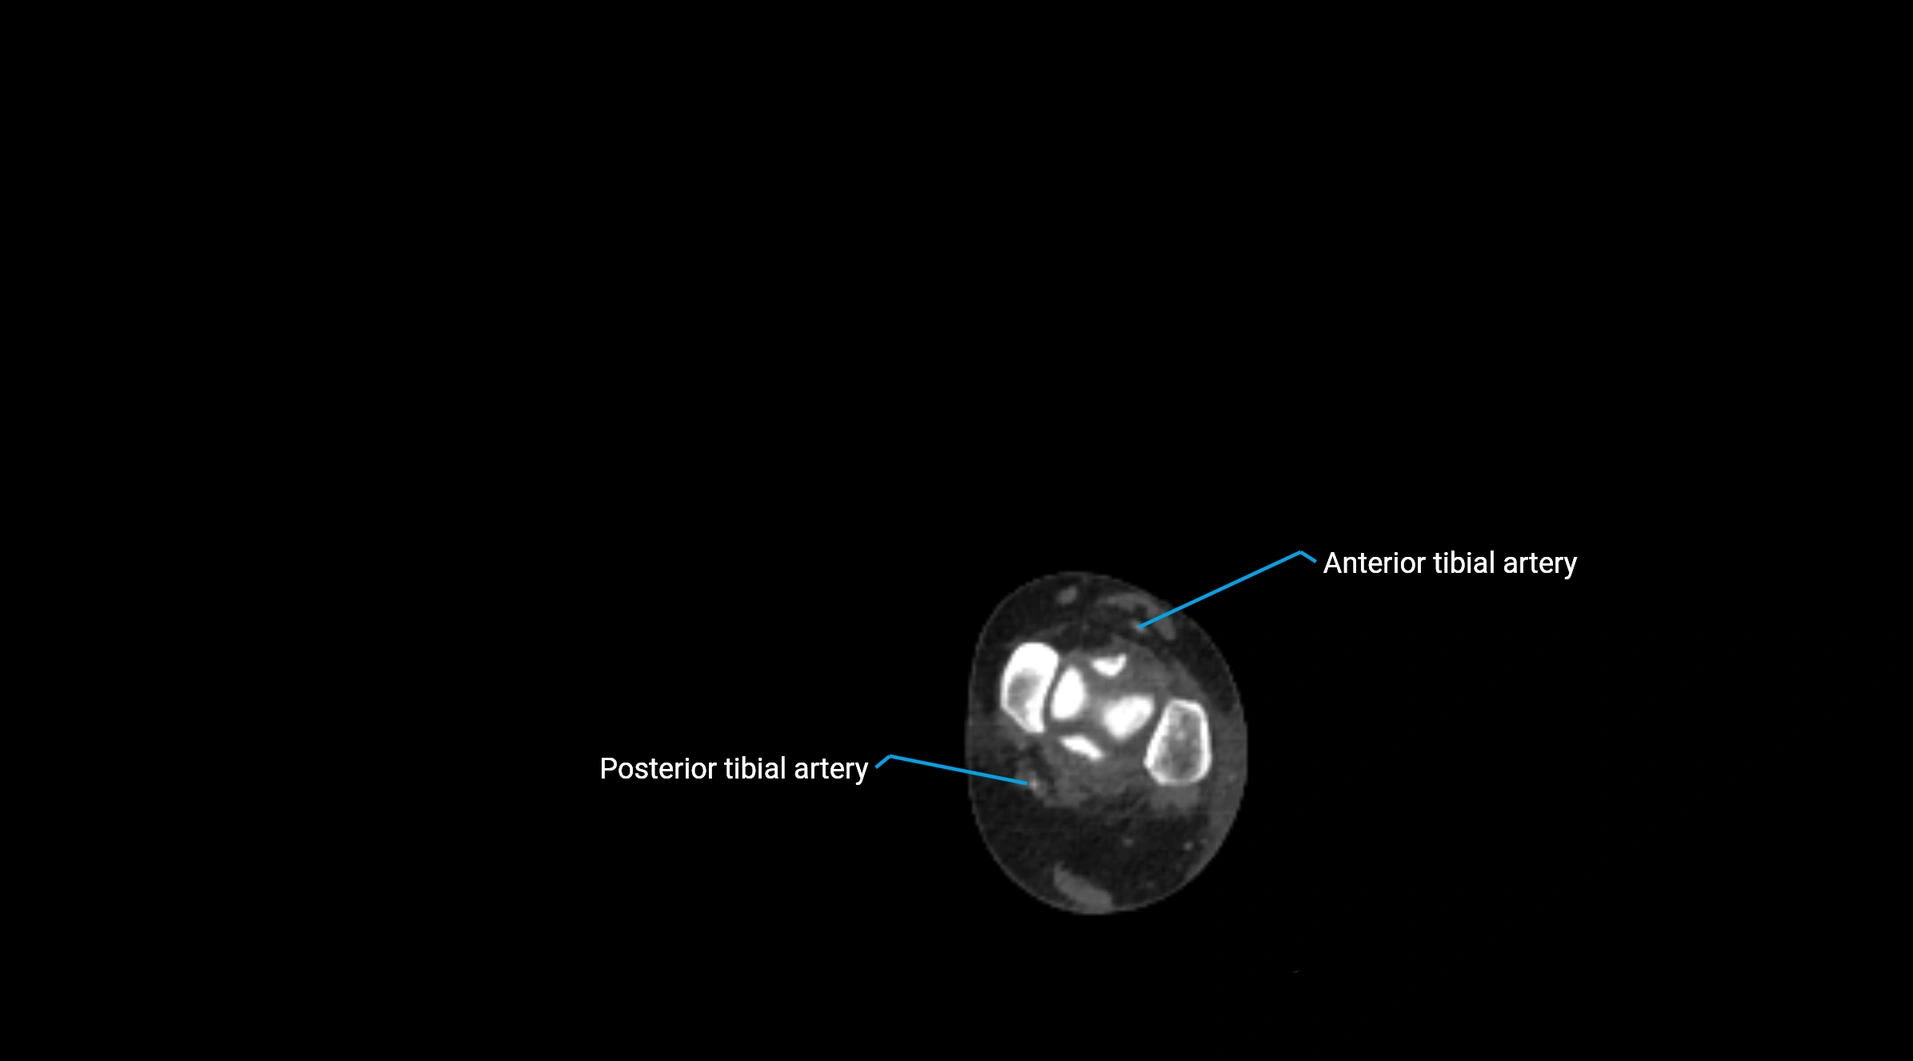

CT Appearance

Non-contrast CT:

• Appears as a tubular soft tissue structure anterior to vertebral bodies

• Calcified atherosclerotic plaques appear as hyperdense foci along the wall

• Useful for screening abdominal aortic aneurysm (AAA) size and mural calcification

Contrast-enhanced CT (CTA):

• Gold standard for abdominal aortic imaging

• Provides excellent detail of lumen, wall, aneurysm, thrombus, and branch vessels

• Multiplanar and 3D reconstructions help in aneurysm measurement, stent graft planning, and dissection evaluation

• Detects acute rupture, traumatic injury, or occlusion with high sensitivity